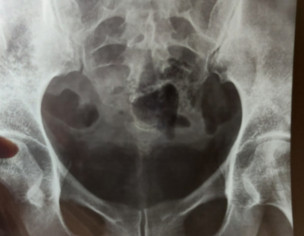

I have pain in my tail bone. Now I have when I sit or stand or lay on bed. Doc said its inflammation HISTORY--> tailbone was injured by falling 2 times at the same spot 5 years ago. I had that similar pain always while sitting or standing for long time but now it has increased n its very painful cant sit in my class. XRAY ATTACHED Thank you in advance